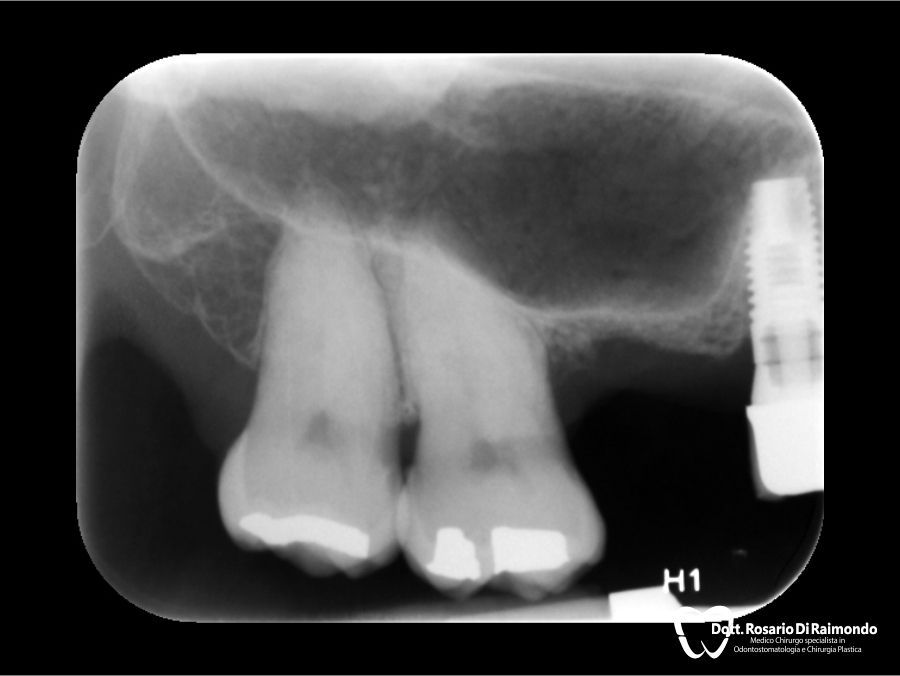

Casi Trattati

Di seguito riportiamo alcune fotografie di casi di Implantologia già trattati.